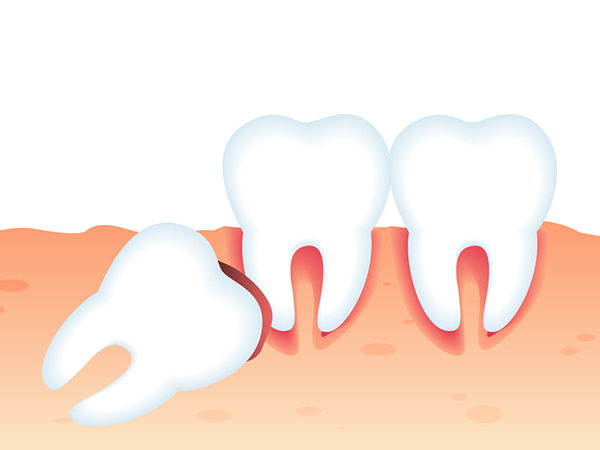

- 사랑니가 누워서 자라는 경우

- 사랑니가 누워서 자라면 바로 앞쪽 어금니 뿌리를 압박해 염증 등의 문제를 일으키거나 앞쪽 어금니와의 사이에 음식물이 잘 끼게되어 충치와 염증을 유발할 수 있습니다.